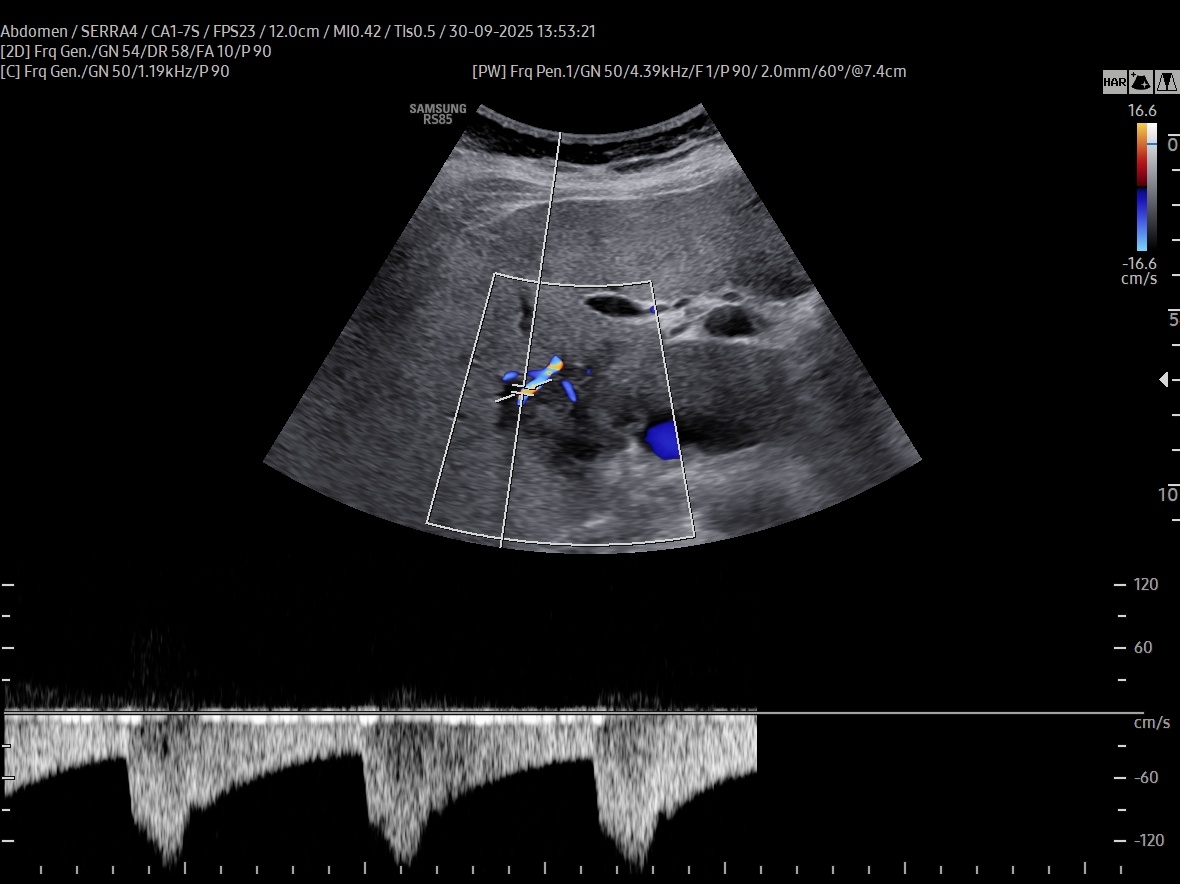

VIDEO 1: On CEUS (Video 1), the lesion exhibited early peripheral rim-like enhancement in the arterial phase, followed by centripetal filling with persistent non-enhancing central areas, likely representing necrotic foci. Washout occurred within one minute, suggesting a cholangiocarcinoma component, either alone or in combination with a hepatocellular component.

On CEUS (Video 1), the lesion exhibited early peripheral rim-like enhancement in the arterial phase, followed by centripetal filling with persistent non-enhancing central areas, likely representing necrotic foci. Washout occurred within one minute, suggesting a cholangiocarcinoma component, either alone or in combination with a hepatocellular component.

Panoramic imaging was subsequently performed: a CT scan followed by MRI confirmed the suspicion of malignancy, without evidence of biliary dilatation or vascular invasion (Figs. 3 and 4); however, a definitive diagnosis could not be established.